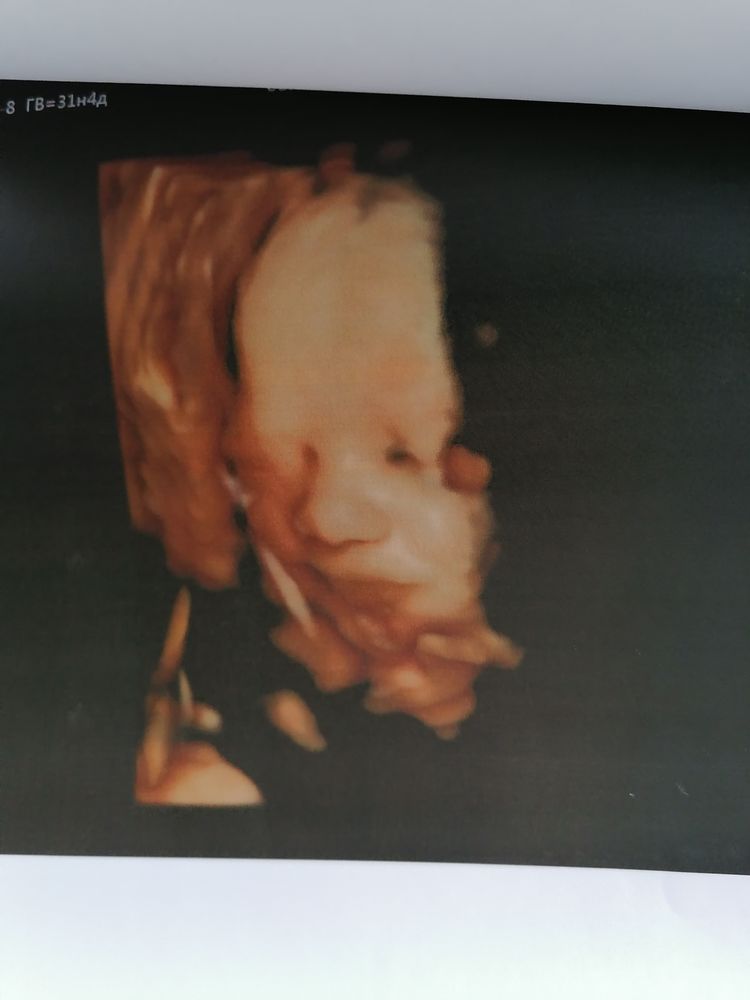

Ну а теперь о сегодняшнем скрининговом узи в 31.4 недели у Пятых Н. С.

Всё как обычно отлично, ощущение, что она нас помнит, все расспросила перед узи, пообщались. Вообщем мы с мужем довольны на все 200%. Очень тщательно рассмотрела каждый орган сыночка. Долго пытались его развернуть что бы увидеть личико и у нас получилось. Включала 4Д узи ждали пока он улыбнётся и опять таки дождались🥰.

По узи с сыночком все тттттт отлично, растёт чётко в срок, уже нет опережение. Все органы на месте, все с ними хорошо. Врач сказала, что очень большие кулачки и ножки🙈. Да я и сама видела, прям такая мужицкая рука и чувствую ух как эти кулачки и ножки🥰.

Весит 1890, что норма для 31.5 недели.

Ну и фоточки сыночка 👶🙏🙏🙏🥰. Люблю его сил нет❤️❤️❤️

Улыбашка мой